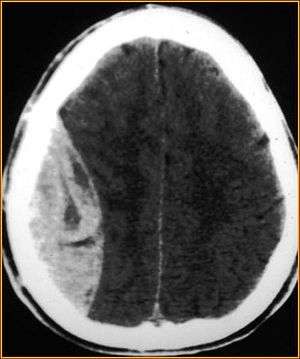

Nontraumatic epidural hematoma in a young woman. The grey area in the top left is organizing hematoma, causing midline shift and compression of the ventricle.

Non-contrast CT Scan of a traumatic acute hematoma in the left fronto-temporal area